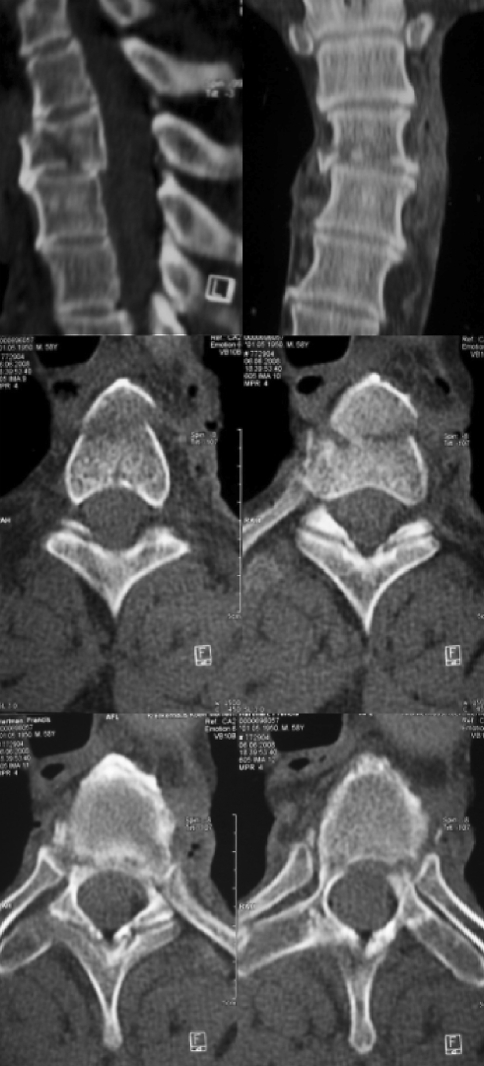

Fig. 1.

Sagittal and coronal profiles of the upper thoracic spine. Unstable fracture type but no spinal canal compromise (upper panel). Sagittal profile of Th3 indicating a coronal split fracture (middle panel) and coronal profile of Th4 with fracture at the pedicle based and the posterior arch (lower panel)